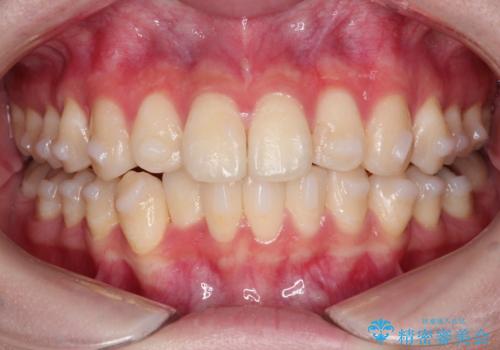

インビザラインによる矯正治療(非抜歯) 前歯の捻れとガタつきの改善

- 上下の前歯に捻れ(捻転)とガタつき(叢生)が見られます。

上の2番目の前歯の捻れに関しては、元々歯の大きさが小さい歯であるため、マウスピースにて力がかかりにくく、捻転の改善が一般的に難しくなりがちです。

下の犬歯に関しても捻れと傾き、ガタつきが大きく、歯根の長さも相まって移動の難易度が高くなりがちです。

インビザラインのそうした特色を踏まえた上で、それらをリカバーできるように治療方式の調整を十分に行い、治療を進めました。

マウスピース枚数 初回33枚 +追加22枚 +追加31枚

概ね2年で治療完了しました。

マウスピース矯正の特性として動かすのが難しい歯を含むケースでしたが、当院独自の工夫を随所に盛り込み、狙い通りの治療結果が得られました。